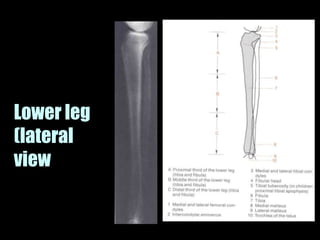

This document provides an overview of normal musculoskeletal imaging. It discusses basic x-ray concepts and densities. It then reviews normal anatomy as seen on x-rays of the skull, spine, pelvis, chest, and extremities. Key anatomical structures are labeled on example x-rays for the shoulder, hip, knee, and foot. Quizzes are included to test recognition of anatomical structures and patient age based on x-rays.